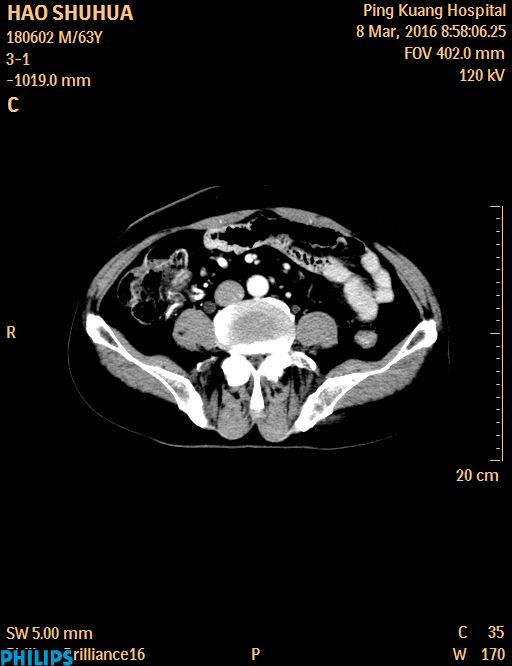

CT51645:盆腔CT

男,63岁,膀胱癌术后1年,发现左腹股沟肿物3个月。

腹壁疝下方软组织密度局部肿块,部分增强,转移?